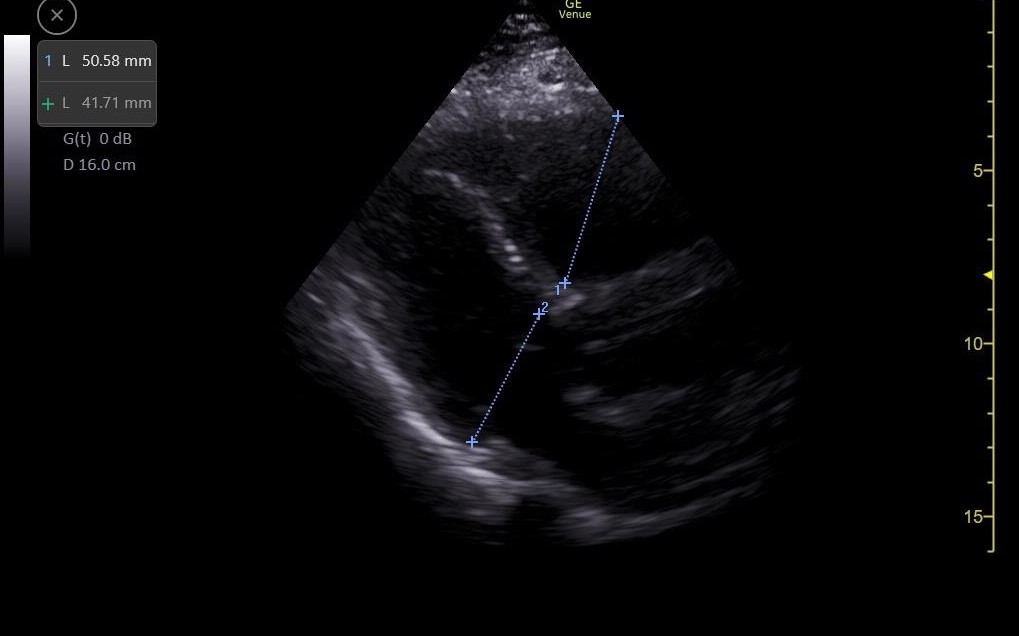

Se realiza ecografía clínica de vasos en miembros inferiores objetivándose un trombo en vena poplítea derecha y ecocardioscopia con dilatación de ventrículo derecho.

Solicitamos electrocardiograma donde se objetiva taquicardia sinusal a 105 lpm y ondas T negativas en V1 y V2, radiografía de tórax sin alteraciones y analítica sanguínea donde destaca DD 156223. Se completa el estudio realizándose angioTC de arterias pulmonares que es informado como tromboembolismo pulmonar bilateral con afectación de todas las ramas lobares bilaterales con imagen compatible con infarto pulmonar en lóbulo superior izquierdo y signos de sobrecarga cardíaca derecha.